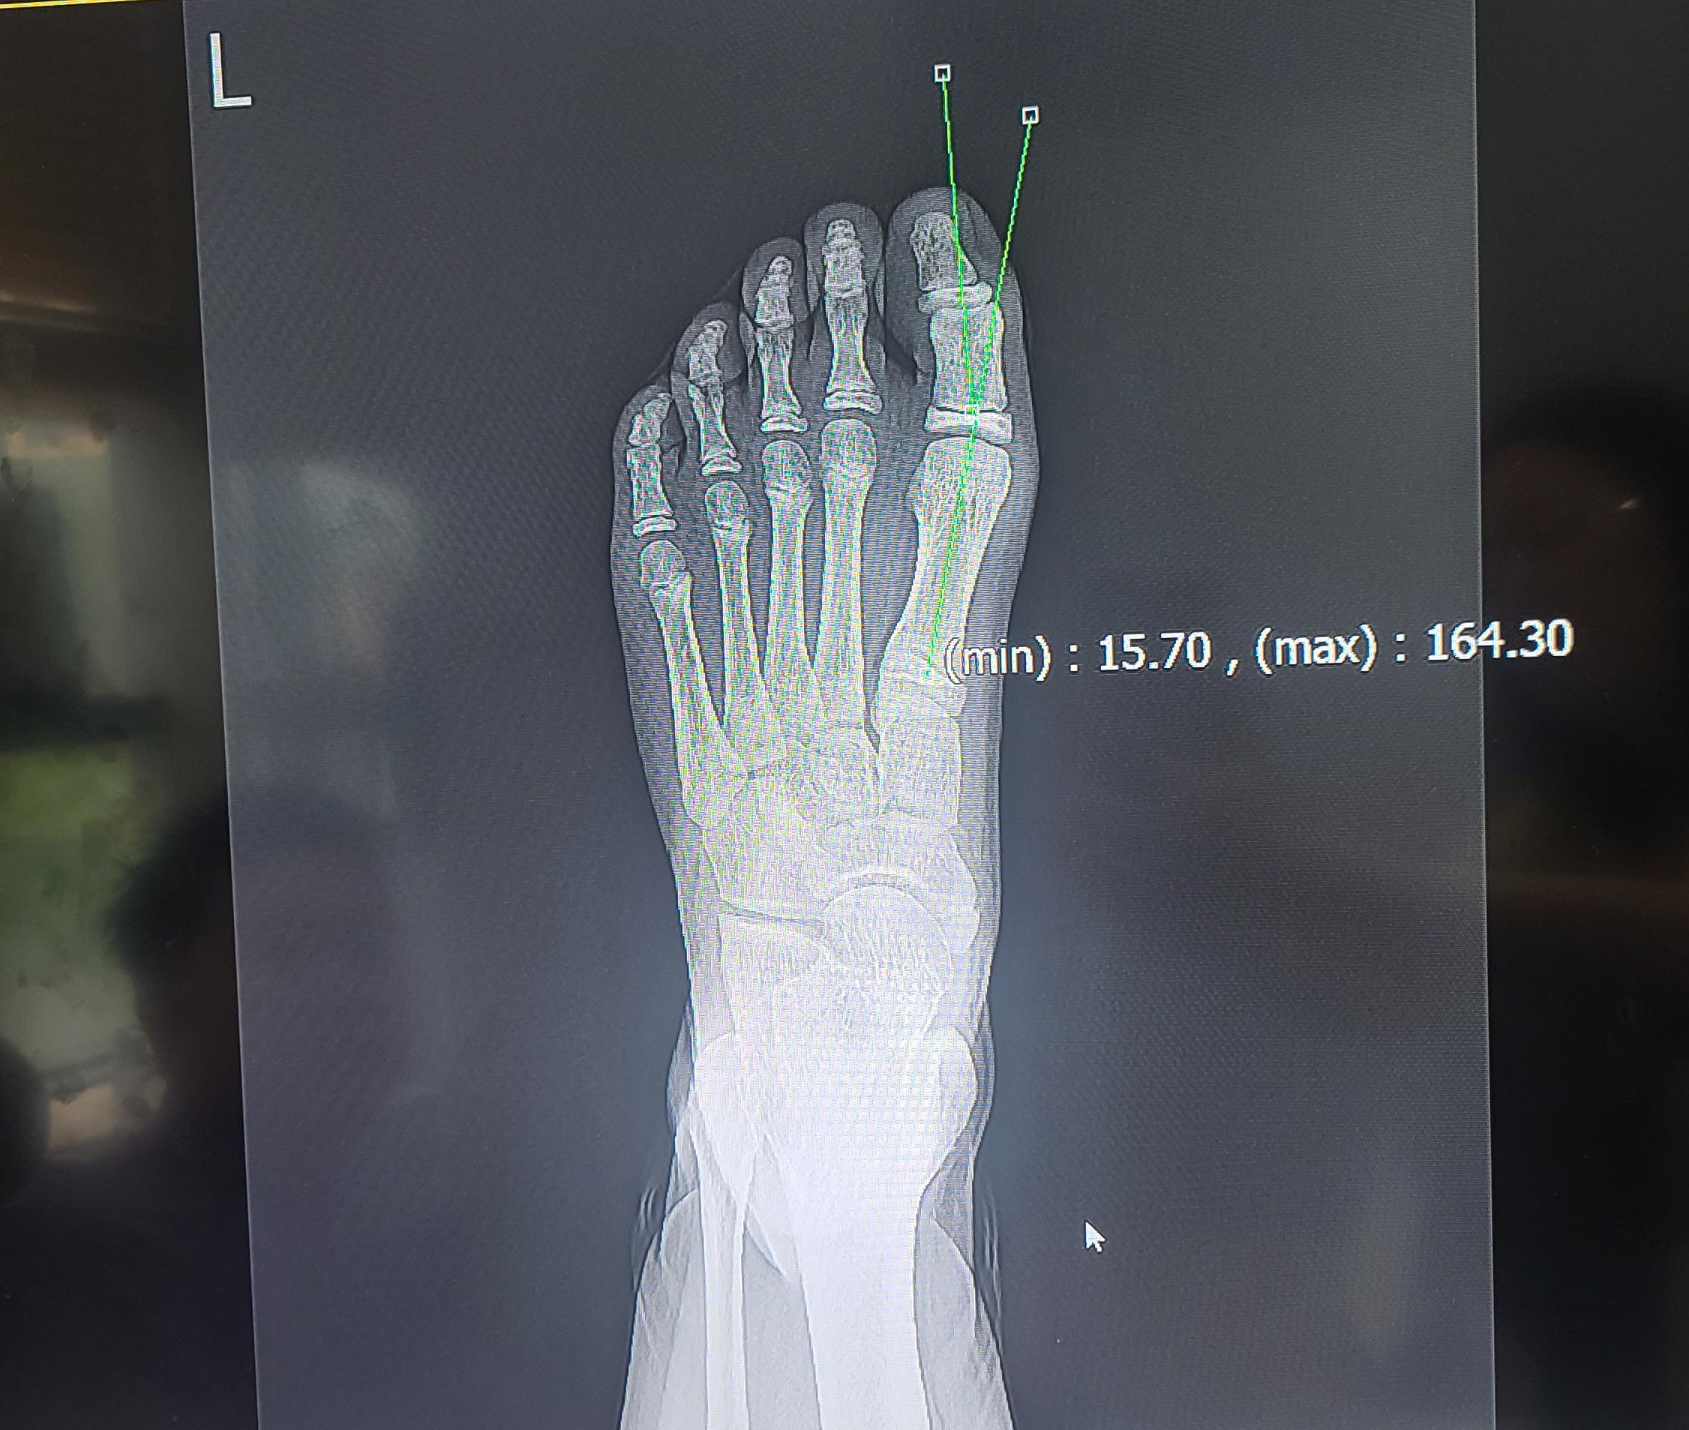

① X-ray 촬영

발을 위에서 찍는 X-ray를 통해 엄지발가락과 발의 각도(보통 15도 이상이면 무지외반증 진단), 관절 상태, 뼈의 변형 정도를 정확히 파악할 수 있습니다.

* 어린이 무지외반증의 중증도 구분

어린이 무지외반증은 진행 단계에 따라 경도, 중등도, 중증으로 나뉘며,

이는 엄지발가락이 휘어진 각도(HVA, 무지외반 각도)와 첫 번째·두 번째 중족골(발등 뼈) 간의 각도(IMA)를 기준으로 분류됩니다.

아래 표는 일반적인 소아 기준에 따라 중증도를 구분한 것입니다.

어린이의 경우 성인보다 발이 유연하고 성장 중이기 때문에, 단순 각도뿐만 아니라 진행 속도, 통증 유무, 기능 제한 여부를 함께 고려해 진단합니다. 따라서, X-ray를 통한 영상 진단과 전문의의 종합적인 평가가 반드시 필요합니다.